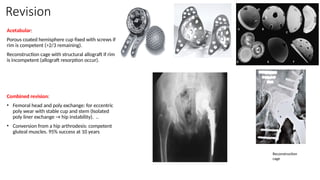

Acetabular:

Porous coated hemisphere cup fixed with screws if

rim is competent (>2/3 remaining).

Reconstruction cage with structural allograft if rim

is incompetent (allograft resorption occur).

Combined revision:

• Femoral head and poly exchange: for eccentric

poly wear with stable cup and stem (Isolated

poly liner exchange → hip instability). ..

• Conversion from a hip arthrodesis: competent

gluteal muscles. 95% success at 10 years

Reconstruction

cage